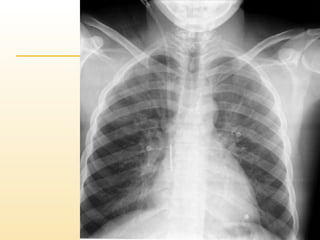

Follow up X- ray:

Catheter tip is

at rt upper

atrium.